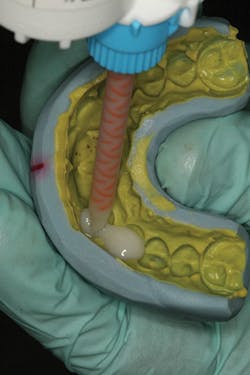

At the beginning of the impression appointment, the provisionals were approved for fit and esthetics with a particular focus on emergence profile of the implant provisionals. Profound anesthesia was achieved and the bisacrylic provisionals were removed. The preparations were cleaned with chlorhexidine (Consepsis, Ultradent) and the abutments were once again removed (figure 10). The open-tray impression copings were then tried in, their seat confirmed radiographically, and then modified into custom impression copings with flowable composite (figures 11-14). Once appropriate tissue support was confirmed, the open-tray master impression was made with a heavy and light body wash technique using vinyl polysiloxane impression material (Honigum, DMG America) (figure 15). Following the master records, the provisional abutments and bisacrylic provisionals were replaced until the seat appointment.

Figure 13

Figure 14